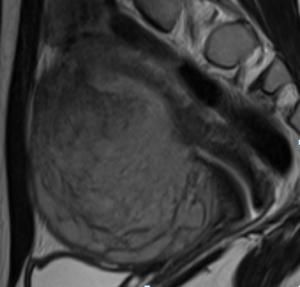

Рис. 2 Эндометриальная стромальная саркома матки низкой степени злокачественности